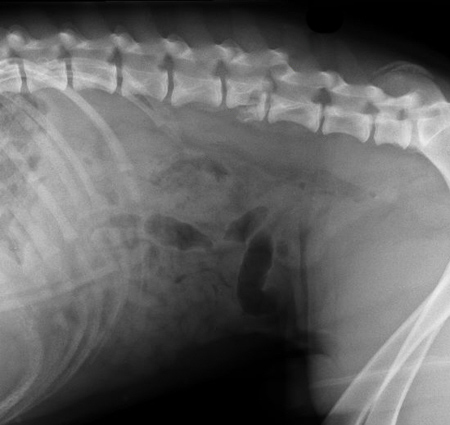

Заболевания позвоночника у домашних животных: диагностика и лечение

Раздел: Визуальные истории